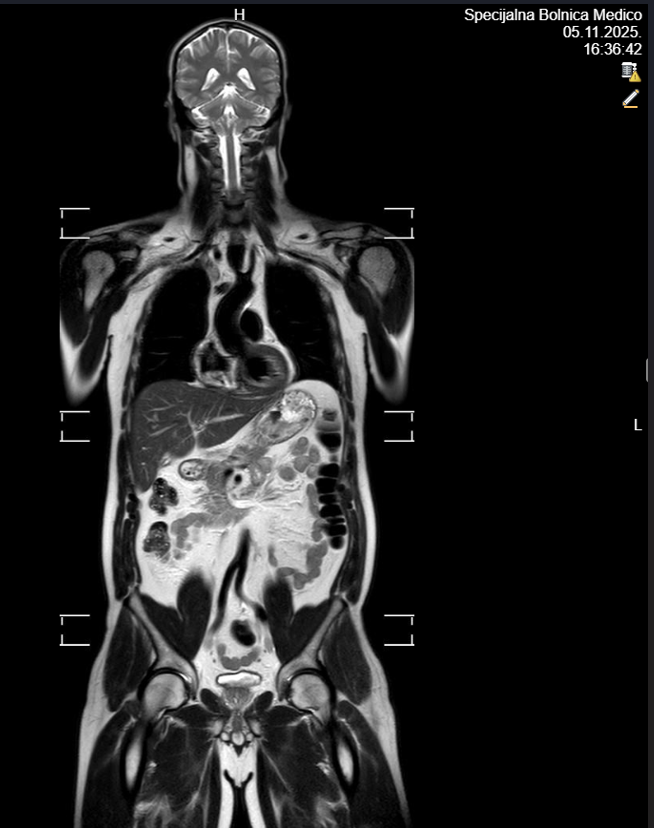

Radi se o bezbolnoj radiološkoj pretrazi koja omogućuje uvid u strukture čitavog organizma tijekom jednog snimanja, bez izlaganja pacijenta ionizirajućem zračenju. Ova metoda smatra se vrlo sigurnom te je najčešće namijenjena osobama s povećanim rizikom za razvoj zloćudnih bolesti, ali i onima koji žele preventivno provjeriti svoje zdravstveno stanje. Osim za ranu detekciju tumora i upalnih procesa, MR cijelog tijela često služi kao dopuna drugim radiološkim pregledima.

U sklopu jednog snimanja, MR omogućuje prikaz mozga, struktura prsnoga koša, trbušnih organa poput jetre, žučnog mjehura, gušterače, slezene i bubrega, zatim nadbubrežnih žlijezda, zdjeličnih organa (mokraćni mjehur, rektum, maternica i jajnici kod žena te prostata kod muškaraca), kao i cijelu kralježnicu – vratnu, prsnu i lumbalnu. Pregled pruža orijentacijski uvid u stanje organizma i može otkriti eventualne promjene koje zahtijevaju dodatnu obradu. Nakon pregleda pacijent dobiva preporuke za daljnju dijagnostiku i eventualne terapijske postupke, čime se olakšava pravovremeno donošenje odluka o zdravstvenoj skrbi.